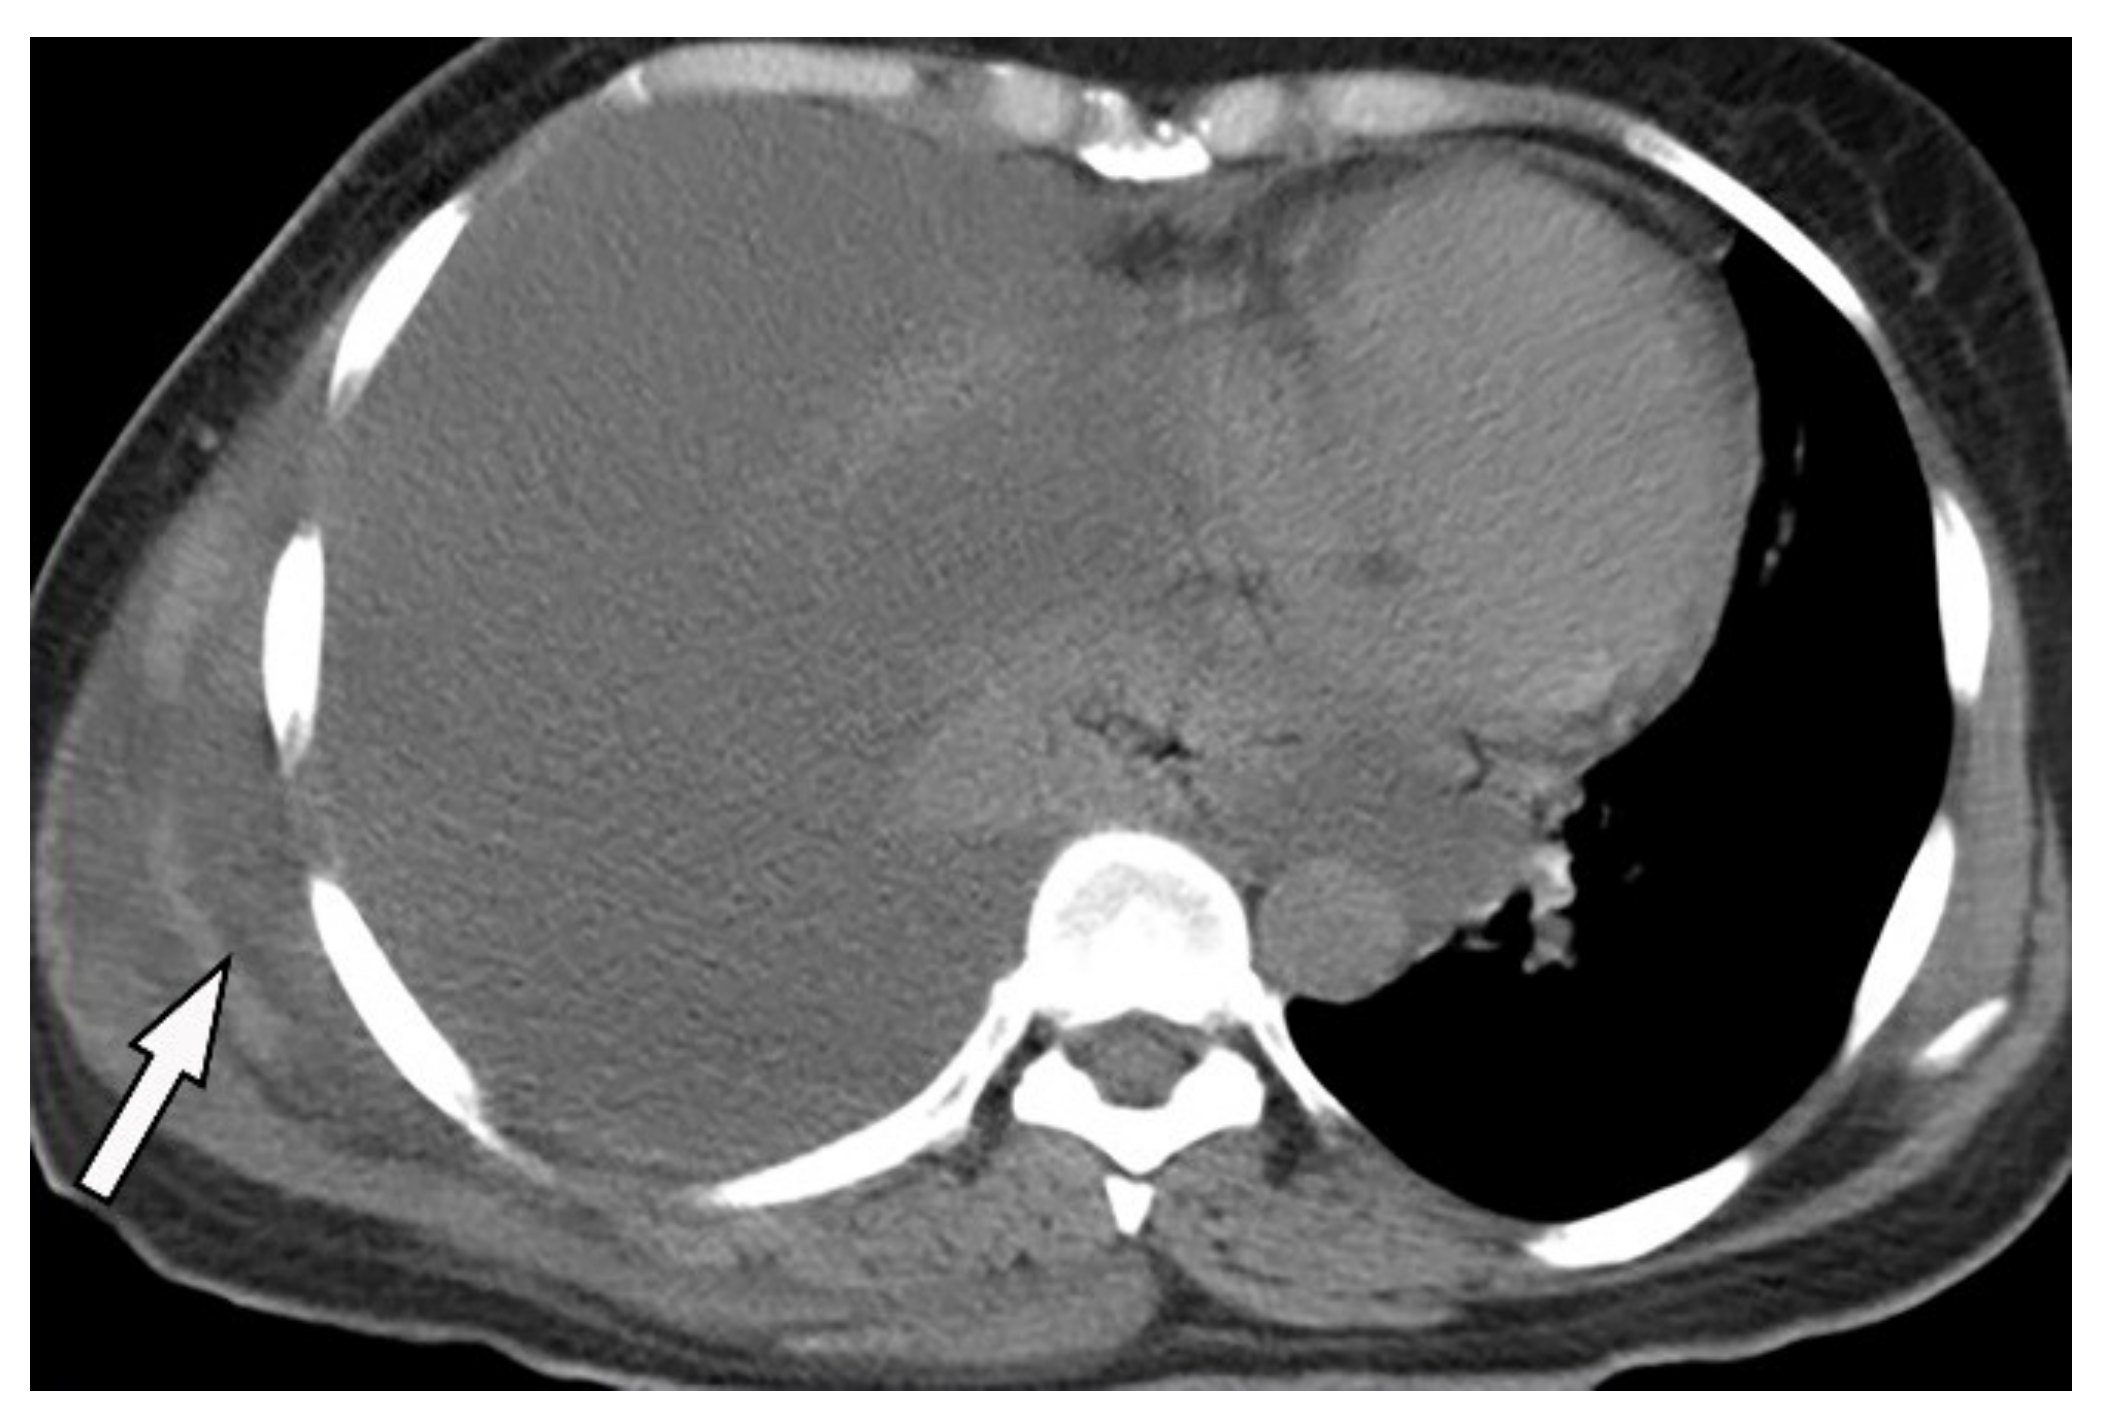

| Empyema necessitance | Connection of pleural collection to extrapleural mass, soft tissue inflammation, rib destruction with periosteal reaction, and fluid collection. | T1W: hypointense effusion and fluid collection T2W: hyperintense effusion, increased thickness of extrapleural fat, and chest wall muscles with hyperintense on T2WFS T1WFS + C: pleural and septal enhancement |